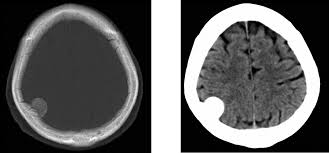

En un estudio de caso-control se exploró la asociación entre el diagnóstico de meningioma que requiere cirugía y el uso previo de anticonceptivos orales que contienen desogestrel o levonorgestrel. Los resultados mostraron un ligero aumento del riesgo de meningioma intracraneal en mujeres que habían usado desogestrel 75 µg durante más de cinco años consecutivos, pero no hubo riesgo en usuarias de levonorgestrel (solo o combinado con estrógeno). BMJ, 11 de junio de 2025.